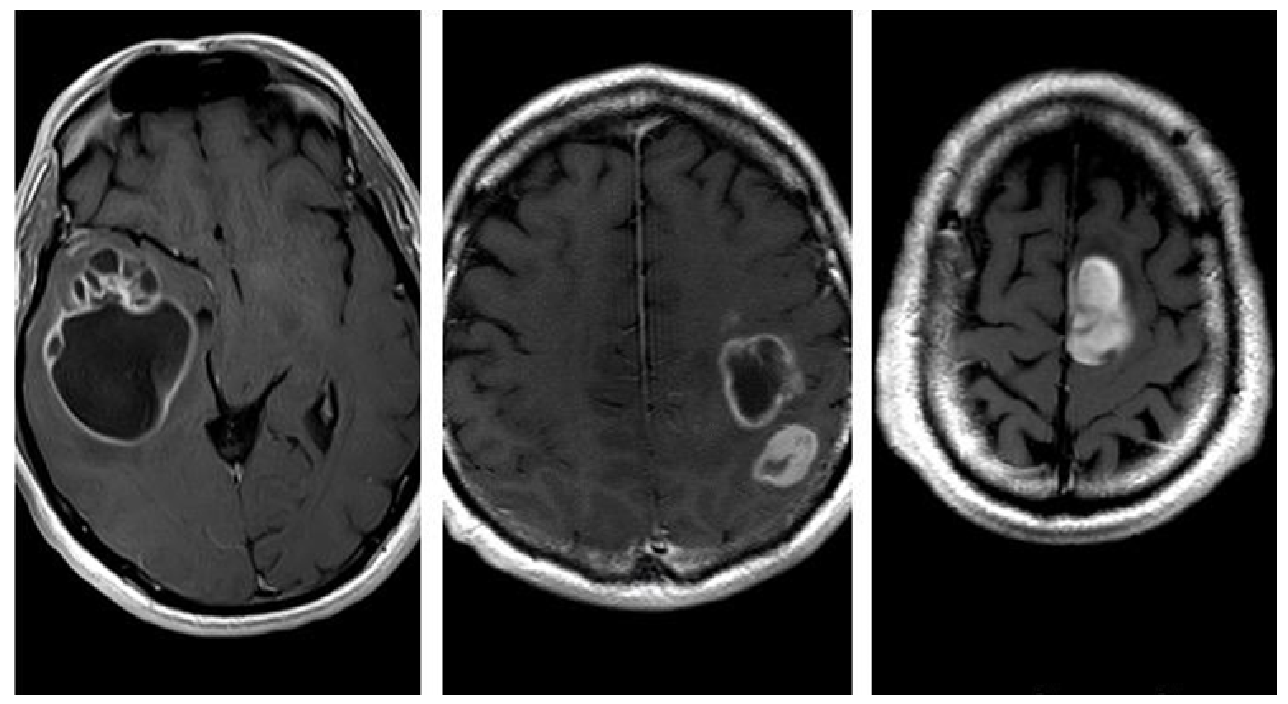

- Morphological appearance: We divided GB lesions into three categories based on the enhancing wall thickness: thin, <3 mm; thin-nodular, when the enhancing wall showed focal thickenings > 3 mm; and nodular, when solid appearance was predominant and intratumoral necrosis was absent or <1.5 cm3. A total of 11 (13%) masses showed a thin pattern, 51 (58%) showed a thin-nodular pattern, and 25 (29%) showed a nodular pattern.

- Multifocal disease: Multifocal disease was found in 20 (23.3%) patients (Table 1).